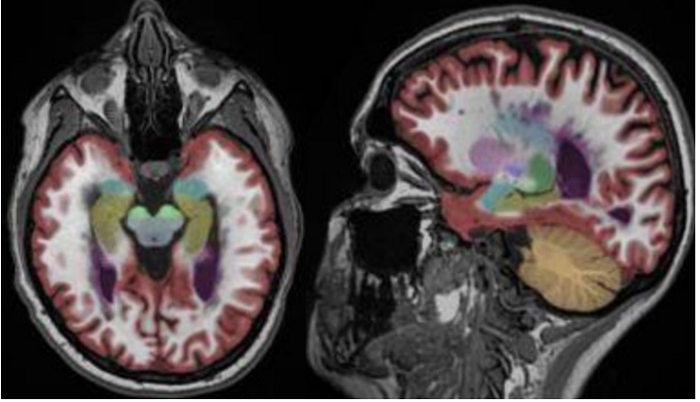

医生诊断用的MRI图像

在现在的医疗机构,医生获取患者的MRI图像后,往往是根据经验判断患者的大脑是否萎缩。因为用经验判断的东西差异化很大,所以漏诊的现象时常出现。

脑医生的云平台工作流程是这样的,医生将受试者数据上传,脑医生通过图像处理、大数据运算和统计学分析等方法将医生的经验量化、标准化,最后得到精确的诊断报告

脑医生系统标注的图像

如上图所示,红色的区域是大脑皮层灰质,这个区域的萎缩是阿尔兹海默症患者重要的早期诊断指标。脑医生系统通过自动标注受试者大脑重要结构的体积与正常指标作对比就可以对受试者情况作出判断

王思伦表示,现阶段脑医生最后给出的诊断报告就像我们平时感冒血常规化验单:白细胞总数12.2(正常5-12),中性粒细胞8.6(正常2-7.8),淋巴细胞比例17.9(正常20-40)……诊断报告标包含大脑重要结构的数据,包括脑灰质白质体积,海马结构及全脑45个重要分区的指标,医生一眼就可以看明白,并给出结论。拿到CFDA认证以后,脑医生会推出带有结论的诊断报告,供医生参考